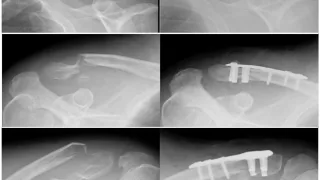

午前の病院での仕事起きたのは, 8時過ぎ.炬燵で眠ってしまいました.急いで朝食を摂って, 妻と一緒に病院へ.昨日深夜〜本日未明に手術を行った上腕骨外顆骨折の子供の経過を診に行くためでした.9時前に病院に到着.妻にはクルマで待機してもらいまし...